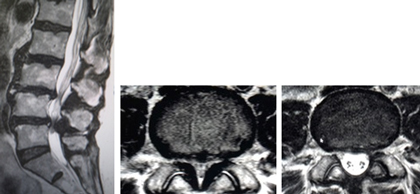

(左、中)術前のMRIでは特に第4/5椎間で脊柱管の高度な狭窄を認めています。(右)棘突起縦割式椎弓形成(切除)術を施行し、脊柱管は著明に拡大し神経症状の改善を認めています。